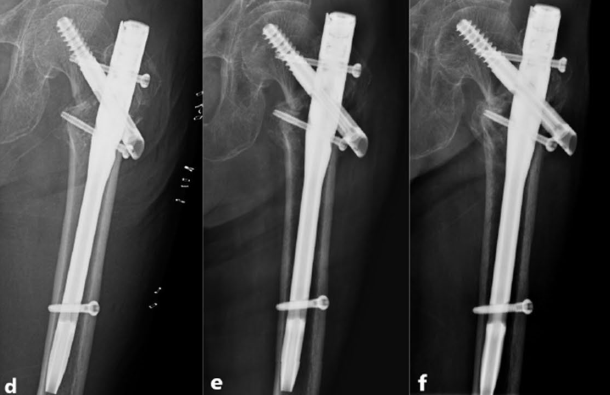

近年来,来自北医三院周方教授团队提出的PFUN,即proximal femoral universal nail system,股骨近端通用髓内钉系统,旨在通过增加内外侧壁的额外固定,即增加小转子螺钉,大转子冠状面螺钉或外侧钢板等,同时重建内外侧壁稳定性:

▲ 图A所示为PFUN系统中,小转子螺钉(c)与外侧壁螺钉(b),图B所示冠状面螺钉(c)。

▲ 图C所示为小转子螺钉(c)与外侧壁钢板(d);图D所示为PFUN三维力图模型。